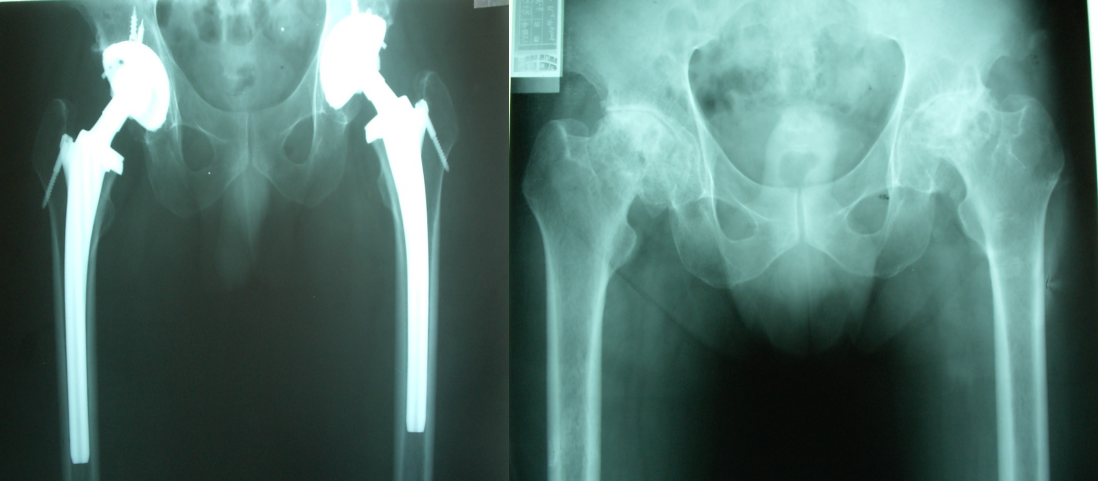

患者髖關(guān)節(jié)治療前后X光片對比圖

【診斷經(jīng)過】脊椎微創(chuàng)科主任、副主任醫(yī)師孫守全為患者進行檢查,發(fā)現(xiàn)左髖部腫脹,壓痛,左側(cè)腹部股溝中心壓痛,大轉(zhuǎn)子叩擊痛,左下肢短縮3cm,余肢體未見異常。通過X線檢查顯示左股骨頸骨折,伴有重度骨質(zhì)疏松。孫主任就病情向潘大爺及他的家屬進行了詳細介紹,建議在硬膜外麻醉下行左股骨頸骨折全髖關(guān)節(jié)置換術(shù)。潘先生當即表示同意。

【治療過程】潘大爺辦理了住院手續(xù)后,經(jīng)一系列術(shù)前檢查,由孫主任為潘大爺在硬膜外麻醉下行左股骨頸骨折全髖關(guān)節(jié)置換術(shù),術(shù)后給予預(yù)防感染,靜脈營養(yǎng)支持,傷肢制動,及對癥處理等治療,患者已經(jīng)能下床行走。